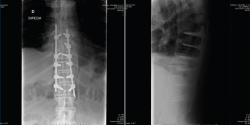

En la Figura 1 se muestra la primera radiografía que le realizan en el centro hospitalario más cercano al accidente. En ella visualizamos un perfil dorsolumbar realizado sobre la camilla de transporte con 2 imágenes. Por un lado, una apertura anterior patológica a través de disco a nivel dorsal, concretamente T10/T11. También observamos una sindesmofitosis de todo el raquis que conocemos como “caña de bambú”. Esto orienta a una enfermedad reumática, concretamente una espondiloartitis anquilosante(1).

Figura 1. Radiografía inicial.